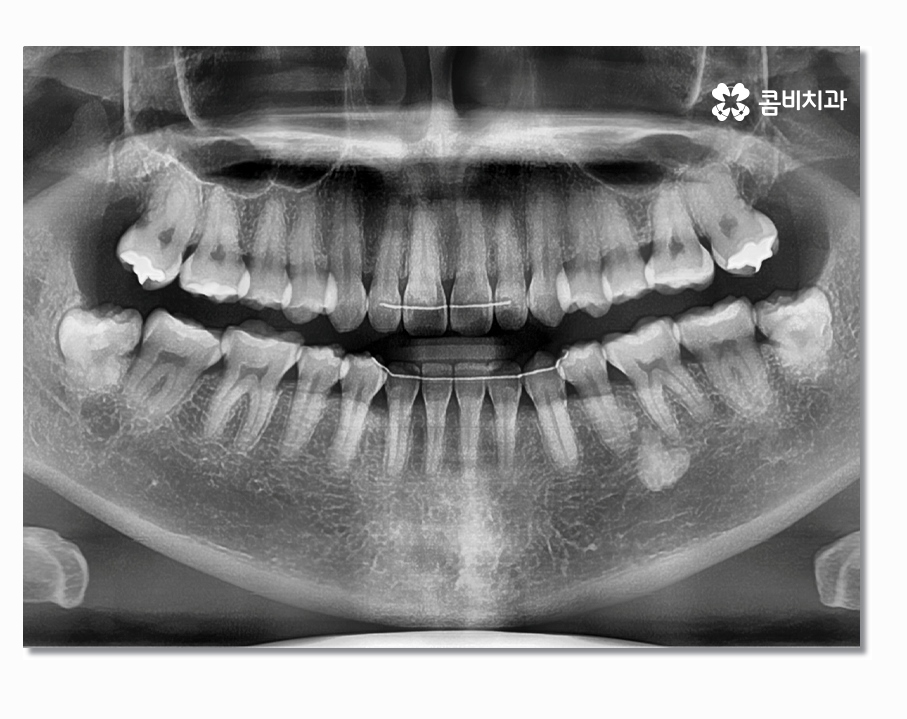

오늘은 부분매복사랑니에 대한 주제로 이야기를 해볼까 하며

부분매복사랑니는 이름 그대로 사랑니가 정상적으로

맹출이 된 것은 아니지만 잇몸 밖으로 부분적으로

나와 있는 상태를 의미하고 있어요.

부분매복사랑니의 경우 치아가 반쯤만 잇몸 위에 맹출 되어 있어서

충치 및 잇몸질환을 일으키기도 하지만 누워서 자라는 형태인

경우도 많은데 이경우 어금니 사이에 충치를 발생시키거나

어금니를 녹게 만드는 경우도 있기 때문에 어금니 손상을 방지하기

위해서라도 발치를 서둘러야 하는 경우가 있어요

사랑니는 겉으로 보이는 것과 X Ray로 살펴보는 것이

큰 차이가 있으며 사랑니의 위치와 맹출 형태, 크기 등에 따라서

발치의 과정부터 시술 난이도의 차이가 있기 때문에

발치를 하기 좋은 시기부터 회복까지 고려하여 시술에 대한

다양한 케이스를 겪어보고 풍부한 임상 경험 및 실력을

갖춘 의료진에게 시술을 받는 것이 바람직하다고 할 수 있어요.